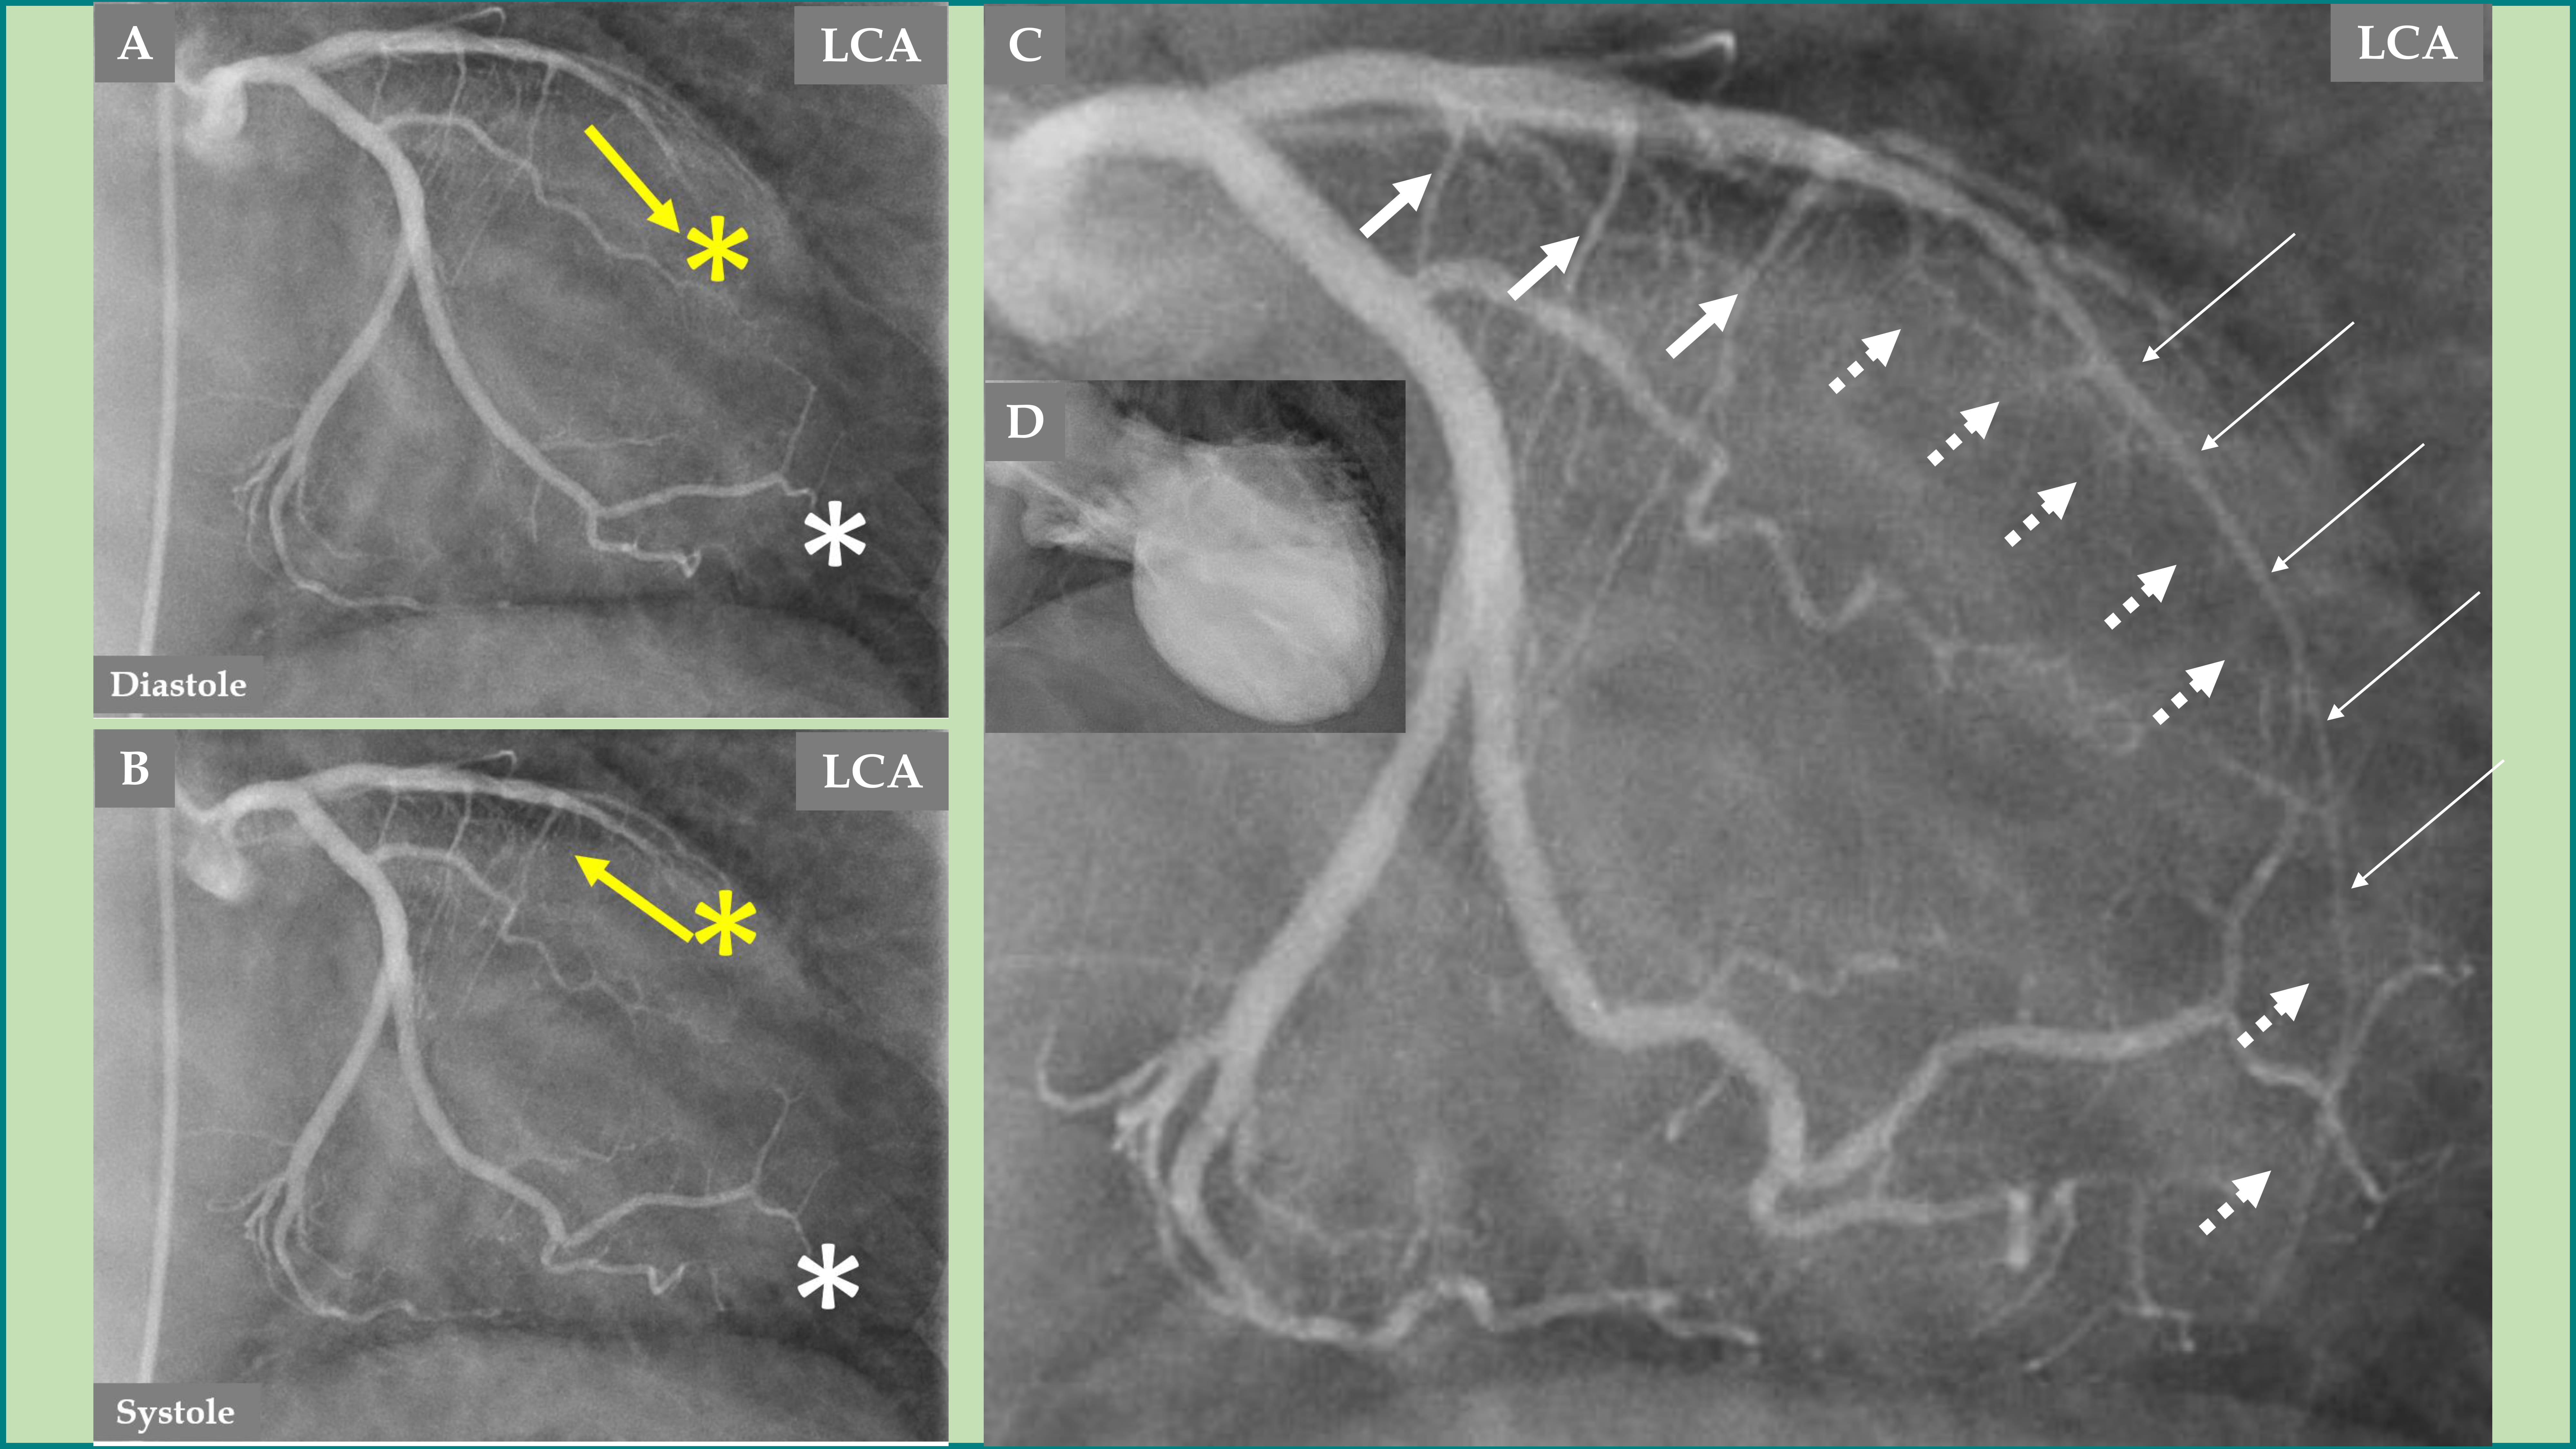

Fig. 5. Comparison of the LCA angiography during the index presentation and follow-up after 5 months. LCA angiography during diastole (A). Contrast left ventriculography during diastole and systole (B). Both (A and B) are during index presentation, where the patient had a clear mid-apical ballooning pattern of TS. LCA angiography during diastole (C). Contrast left ventriculography during diastole and systole (D). Both (C and D) are during the follow-up, 5 months after the index presentation, where there was complete normalization of left ventricular function. The LAD has a normal diameter in the proximal segment and normal three septal branches in both (A and C); meanwhile, the distal two-thirds of the LAD is thin and compressed (A, broken thin long white arrows), and the LAD is almost normal (C, thick long white arrows) during follow-up. The septal branches from the distal two-thirds of the LAD are practically invisible (A, short broken white arrows). The septal branches from the distal two-thirds of the LAD (C, short white arrows) are clearly seen. There are no signs of coronary artery-left ventricular micro-fistulae (CALVMF) during the index presentation (A, yellow question marks). Clear signs of CALVMF are observed around the distal segment of the LAD in the projection; however, CALVMF are most probably from the distal marginal branch (C, yellow arrows) when all projections of LCA angiography have been analyzed. This figure clearly shows that the LAD, the septal branches, and CALVMF were compressed by the myocardial stunning during the index presentation and were relieved during follow-up when the left ventricular function is completely normalized.

An interesting finding, which forms a novel observation, is that no signs of CALVMF was observed during the index presentation with a mid-apical ballooning pattern of TS (Fig. 3C and Fig. 5A); however, during follow-up coronary angiography when the left ventricular dysfunction has completely normalized, there was clear signs of CALVMF, most probably arising from the distal marginal branches (Fig. 4A,C during diastole and systole and Fig. 5C). It is also clearly seen that the contrast staining moves to the left ventricular cavity during systole (Fig. 4C). These micro-fistulae were not visible during index presentation because of the compression by the myocardial stunning (myocardial cramp) caused by TS. The comparison between the index presentation, where there were no signs of CALVMF, and the follow-up 5 months later, where signs of CALVMF appeared clearly, is demonstrated in Fig. 5.